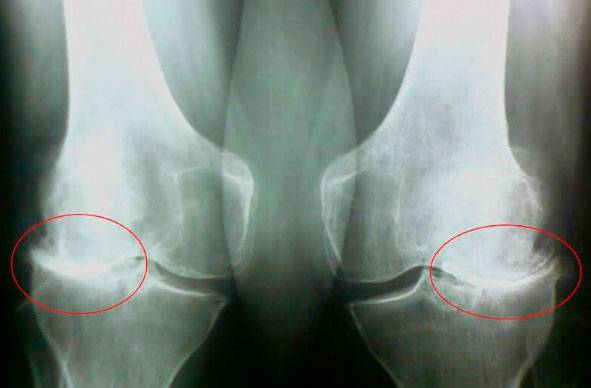

Guarda queste immagini, puoi vedere che nell'immagine a destra manca lo spazio articolare, le ossa si sfregano tra loro e causano un dolore intenso. E questo processo è molto difficile da fermare! Dopo un paio d'anni, una persona sarà disabile e non sarà in grado di prendersi cura di se stessa.

Nicola Milanesi: La prima cosa sono le lesioni e i carichi gravi. Il sovrappeso esercita anche molta pressione sulle articolazioni. La vita sedentaria, lo stress, una grande quantità di sale e zucchero negli alimenti, tutto ciò ammorbidisce il tessuto cartilagineo, lo consuma e lo assottiglia. Con ogni nuovo movimento, la cartilagine si consuma e si deforma, le ossa iniziano a sfregarsi tra loro, provocando un dolore insopportabile .